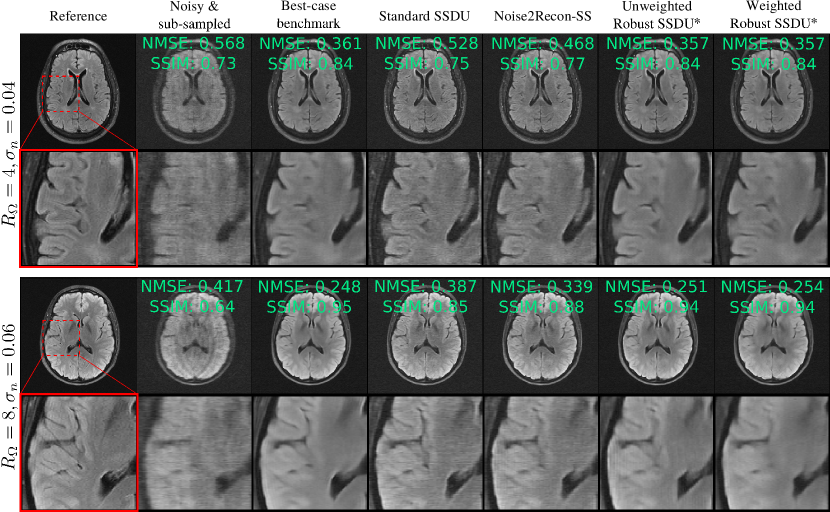

Figure 7: Example reconstructions for networks trained on noisy, sub-sampled data. The proposed methods, highlighted with an asterisk, perform very similarly to the best-case benchmark, even at RΩ=8subscript𝑅Ω8R_{\Omega}=8.

V-D Task B: Sub-sampled, noisy training data

Fig. 8 shows the test set loss for the methods designed for sub-sampled, noisy training data. The weighted and unweighted variants of the proposed Robust SSDU performed within 0.17dB of the best-case benchmark, despite only having access to noisy, sub-sampled training data. Noise2Recon-SS performs well in some cases, particularly at RΩ=4subscript𝑅Ω4R_{\Omega}=4, but is consistently outperformed by both variants of Robust SSDU. Fig. 7 shows example reconstructions, demonstrating similar performance to the best-case benchmark qualitatively. Fig. 9 compares Standard SSDU and Weighted Robust SSDU using clinical expert bounding boxes from fastMRI+ [36], which shows that the proposed method has substantially enhanced pathology visualization.

The examples in figures 5, 7 and 9 show that proposed methods are qualitatively very similar to the best-case benchmark, and substantially improve over methods without denoising, whose reconstructions are visibly corrupted with measurement noise. The examples exhibit some loss of detail and blurring at tissue boundaries, especially at RΩ=8subscript𝑅Ω8R_{\Omega}=8. However, the extent of detail loss is similar in the benchmark, indicating that the loss of detail is not a limitation of the proposed methods. Rather, the qualitative performance is limited by the other factors such as the architecture, dataset and choice of loss function. This can also be explained in part by noting that the high-frequency regions of k-space, which provide fine details, typically have smaller signal so are particularly challenging to recover in the presence of significant measurement noise.